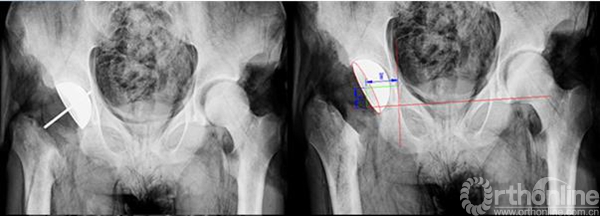

我们将对照侧髋臼表面点云的最适拟合球心坐标的镜像定义为HJC。通过3-matic6.1 软件建立水平位和冠状位的辅助平面,分别获得骨盆二维平面上的投影并测量得到髋关节的旋转中心O1和髋臼的方位(如图7)。再通过三角函数的关系计算得到髋臼旋转轴上的一个点(O2)(如图8)。连接O1O2两点的直线就代表了髋臼的旋转轴,也就是模板导航管的方向,沿计算好的髋臼旋转轴植入一虚拟髋臼杯假体,可以实现三维可视化观察,判断预期臼杯植入的效果(如图9)。

图7通过骨盆冠状面、水平面两个投影平面测得髋臼方位。

图8 图中O1为髋中心,利用三角函数的关系计算得到髋臼旋转轴上的O2。

图9 将虚拟髋臼杯沿髋臼旋转轴线植入到髋臼进行模拟观察。

辅图 实验后的X线平片,据其测量臼杯假体方位。

辅图 尸体实验臼杯假体植入后的CT影像。

研究表明,通过建立骨盆的辅助平面,结合三维信息的采集和二维平面的测量获得的髋臼外展角和髋臼前倾角更加接近其生理角度。以健侧为参照,根据对称性原理建立模板侧髋臼方位具有可靠的精确度,又避免了变异的解剖特点对测量结果的影响。